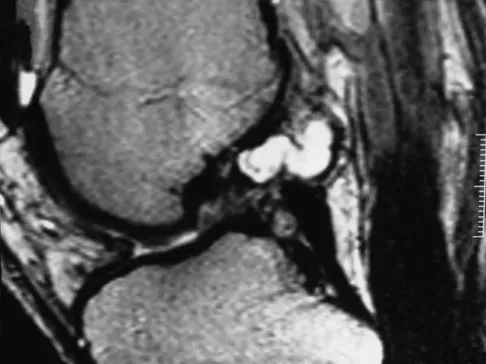

Question 61

A 17-year-old boy has had elbow pain for the past 6 weeks. A radiograph, MRI scans, and biopsy specimens are shown in Figures 65a through 65e. What is the most likely diagnosis?

Explanation